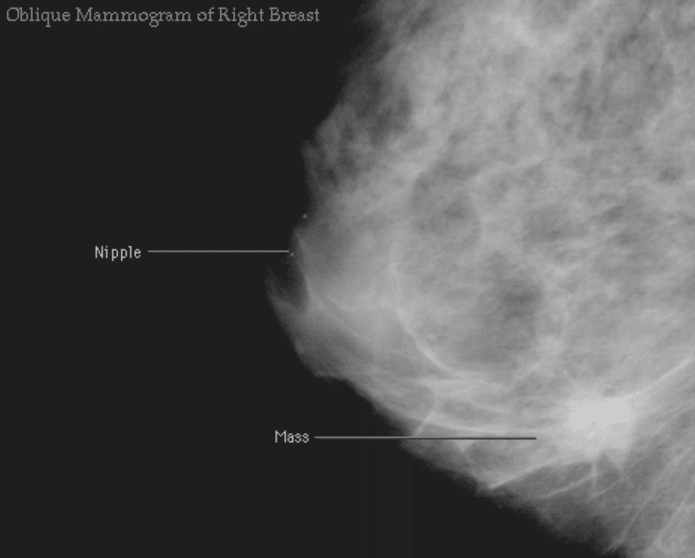

Mamografia

Os achados clássicos de câncer de mama em mamografias geralmente incluem a presença de uma massa ou densidade de tecido mole e microcalcificações suspeitas.

A característica mais específica é uma massa espiculada de alta densidade, que representa um câncer invasivo em quase 90% dos casos.